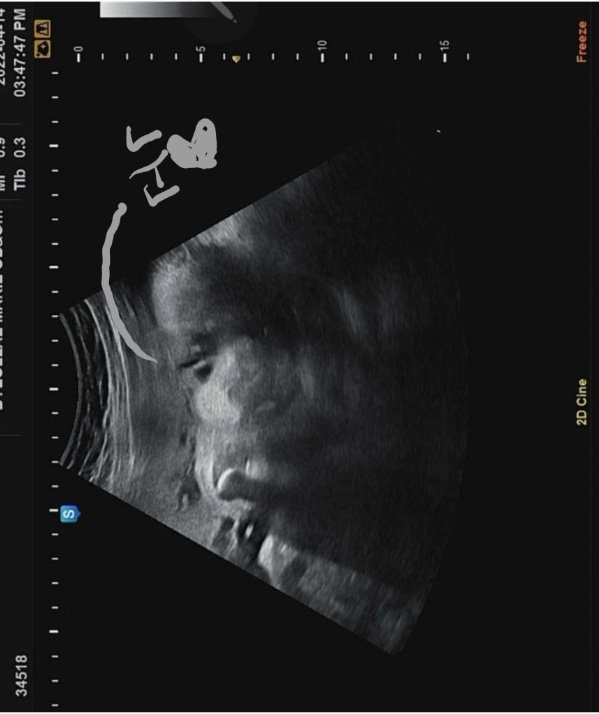

차츰 주수가 늘어날수록 초음파 영상에 꽉 차는 까꿍이 모습. 이제는 양수가 줄어들면서 태아가 차지하는 공간이 많아지는 시기기 때문에 더 그러는 것 같다. 제한된 공간에서 손을 웅크리고 있는 까꿍이. 역시나 얼굴보기 힘들었지만 잠깐이나마 가까스로 언 듯 보이는 까꿍이 얼굴이 너무 반갑다.